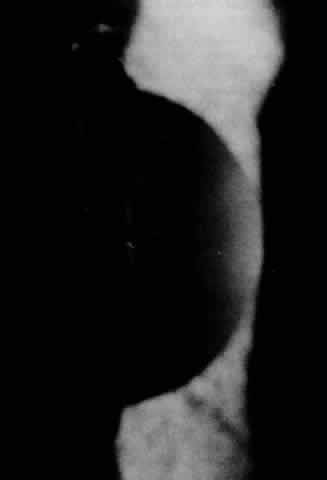

Clinically, the cornea has a ground-glass appearance owing to significant stromal edema, but the epithelium only shows a granular appearance without staining (Fig. 13). No bullous changes are seen. Band keratopathy may be an associated finding. Erosions are unusual. Visual acuity ranges from 20/50 to light perception. No consistent systemic findings have been demonstrated. However, one family displayed an autosomal dominant pattern in which high-tone sensory deafness was present. The parents were first cousins.205 Family history and clinical findings are important in differentiating this dystrophy from other diseases.206,207 It is especially important to rule out congenital glaucoma which requires different management. Consanguinity may increase risk of systemic problems.

Fig. 13. Congenital hereditary endothelial dystrophy: haziness secondary to edematous thickened stroma.